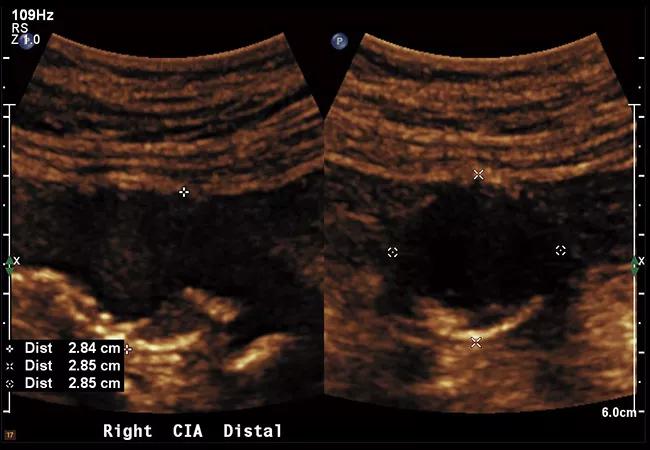

Ultrasound images of isolated CIAAs with diameters of 2.7 cm (top panel) and 4 cm (bottom panel).